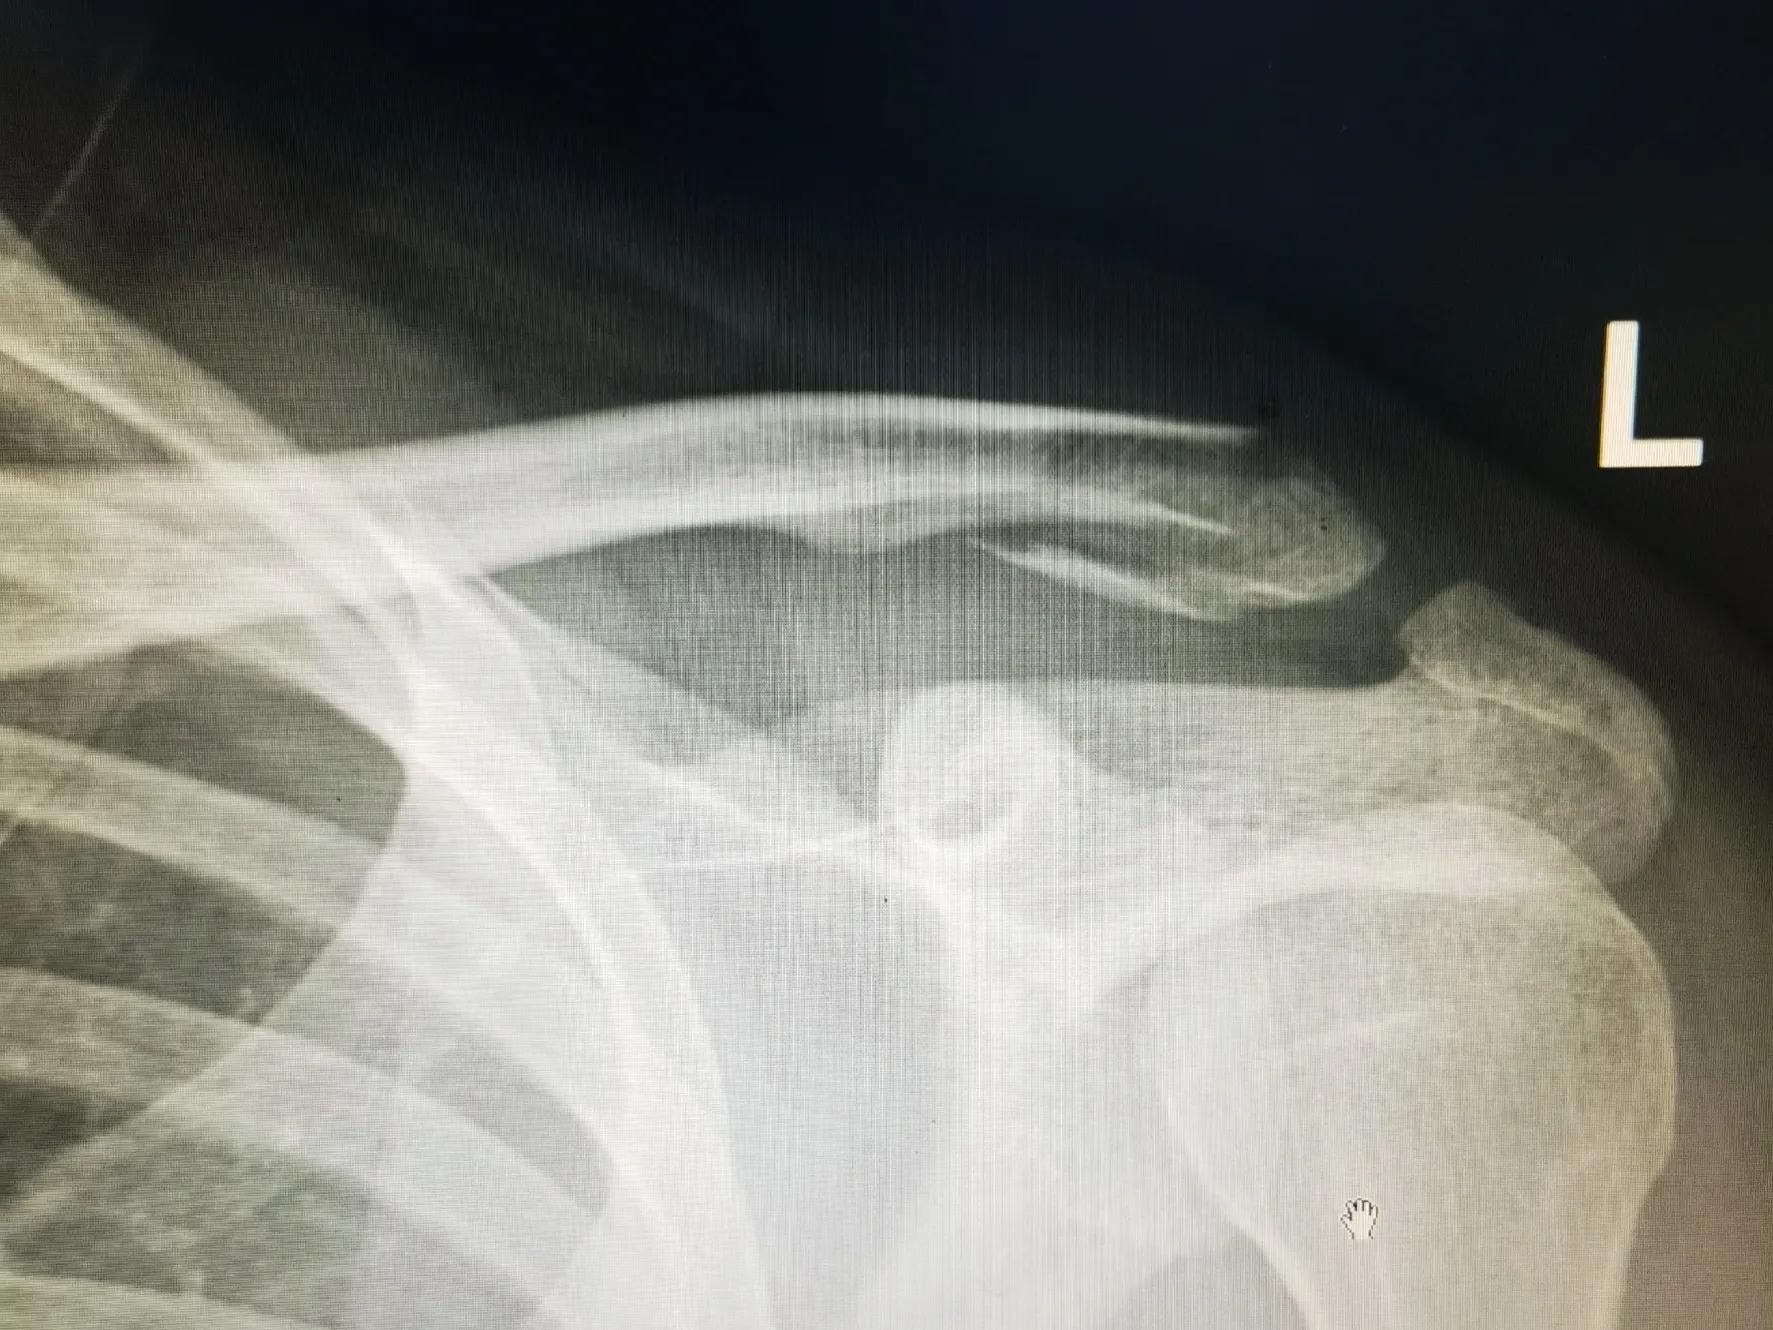

锁骨远端骨折

锁骨远端骨折切开复位袢钢板内固定